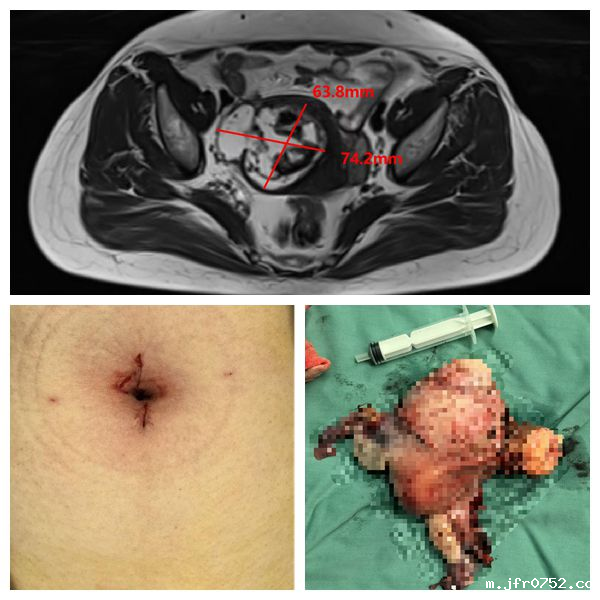

近日,妇瘤病院四病区王国庆主任医师团队,在手术麻醉部的密切配合下,运用第四代“达芬奇”机器人系统,成功开展我院首例单孔达芬奇机器人全子宫双附件手术,这一创新...